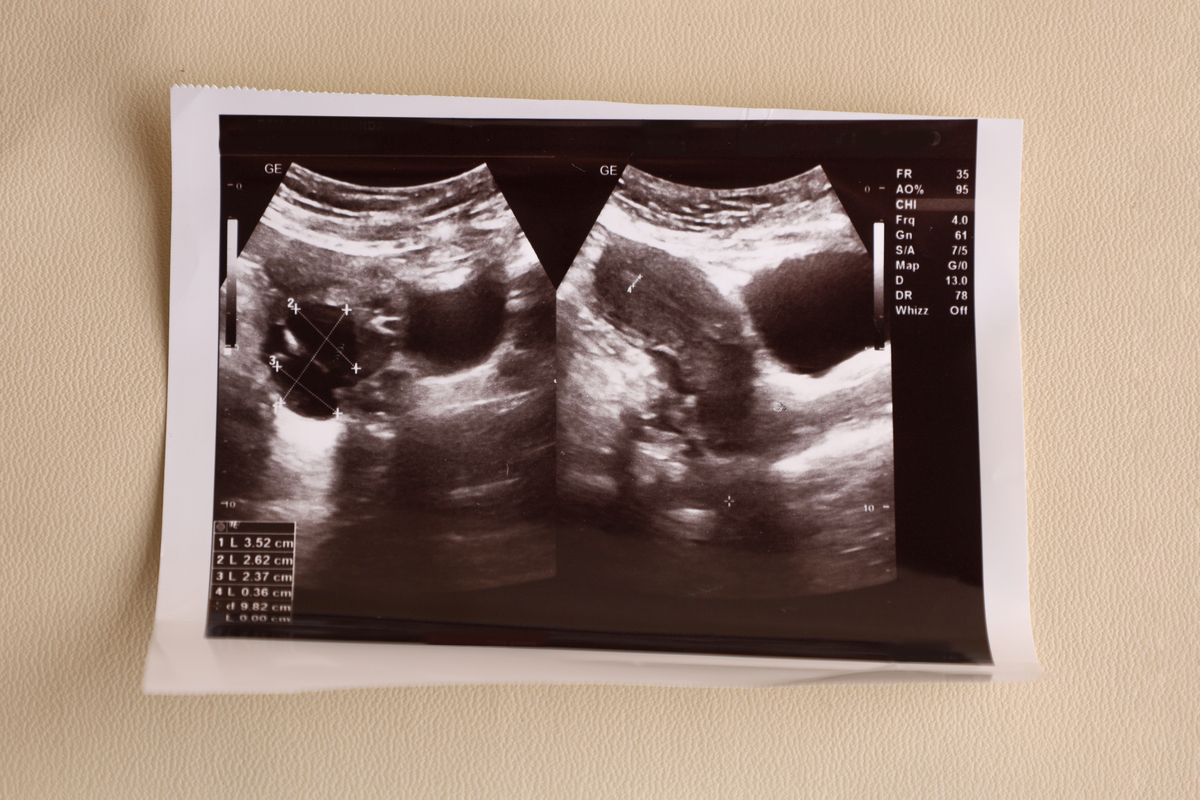

产后妇女前盆腔评估:经会阴超声技术的应用与评价

评价:这是一项针对产后妇女的前盆腔评估研究,使用经会阴超声技术进行评估。